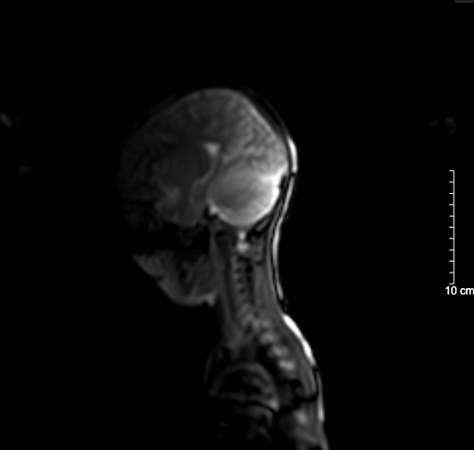

Kết quả chụp não, cột sống cổ bệnh nhi sau 5 ngày nhập viện bình thường

BSCKII. Doãn Phúc Hải - Trung tâm Nhi khoa, Bệnh viện Bạch Mai trực tiếp điều trị cho bệnh nhi chia sẻ: Thân nhiệt của bệnh nhi được hạ nhanh xuống và kiểm soát duy trì ở mức 34°C, giảm tổn thương, tái tưới máu tại não, tăng tỉ lệ sống và hồi phục chức năng thần kinh. Sau 72 giờ điều trị hạ thân nhiệt chủ động, bệnh nhi được nâng thân nhiệt, làm ấm trở lại về mức bình thường và duy trì theo dõi trong 48 giờ. Khi thân nhiệt trở lại bình thường, bệnh nhi tỉnh dần và được rút ống thở. Dấu hiệu sinh tồn ổn định, tri giác nhận thức tốt. Sau 5 ngày nằm viện, bệnh nhi đã tỉnh táo hoàn toàn. Kết quả chụp tim, phổi, MRI sọ não, cột sống cổ không thấy bất thường. Đây cũng là trường hợp đầu tiên trẻ 5 tuổi tự “thắt cổ” mà chúng tôi bắt gặp.

Kết quả chụp não, cột sống cổ bệnh nhi sau 5 ngày nhập viện bình thường

BSCKII. Doãn Phúc Hải - Trung tâm Nhi khoa, Bệnh viện Bạch Mai trực tiếp điều trị cho bệnh nhi chia sẻ: Thân nhiệt của bệnh nhi được hạ nhanh xuống và kiểm soát duy trì ở mức 34°C, giảm tổn thương, tái tưới máu tại não, tăng tỉ lệ sống và hồi phục chức năng thần kinh. Sau 72 giờ điều trị hạ thân nhiệt chủ động, bệnh nhi được nâng thân nhiệt, làm ấm trở lại về mức bình thường và duy trì theo dõi trong 48 giờ. Khi thân nhiệt trở lại bình thường, bệnh nhi tỉnh dần và được rút ống thở. Dấu hiệu sinh tồn ổn định, tri giác nhận thức tốt. Sau 5 ngày nằm viện, bệnh nhi đã tỉnh táo hoàn toàn. Kết quả chụp tim, phổi, MRI sọ não, cột sống cổ không thấy bất thường. Đây cũng là trường hợp đầu tiên trẻ 5 tuổi tự “thắt cổ” mà chúng tôi bắt gặp.